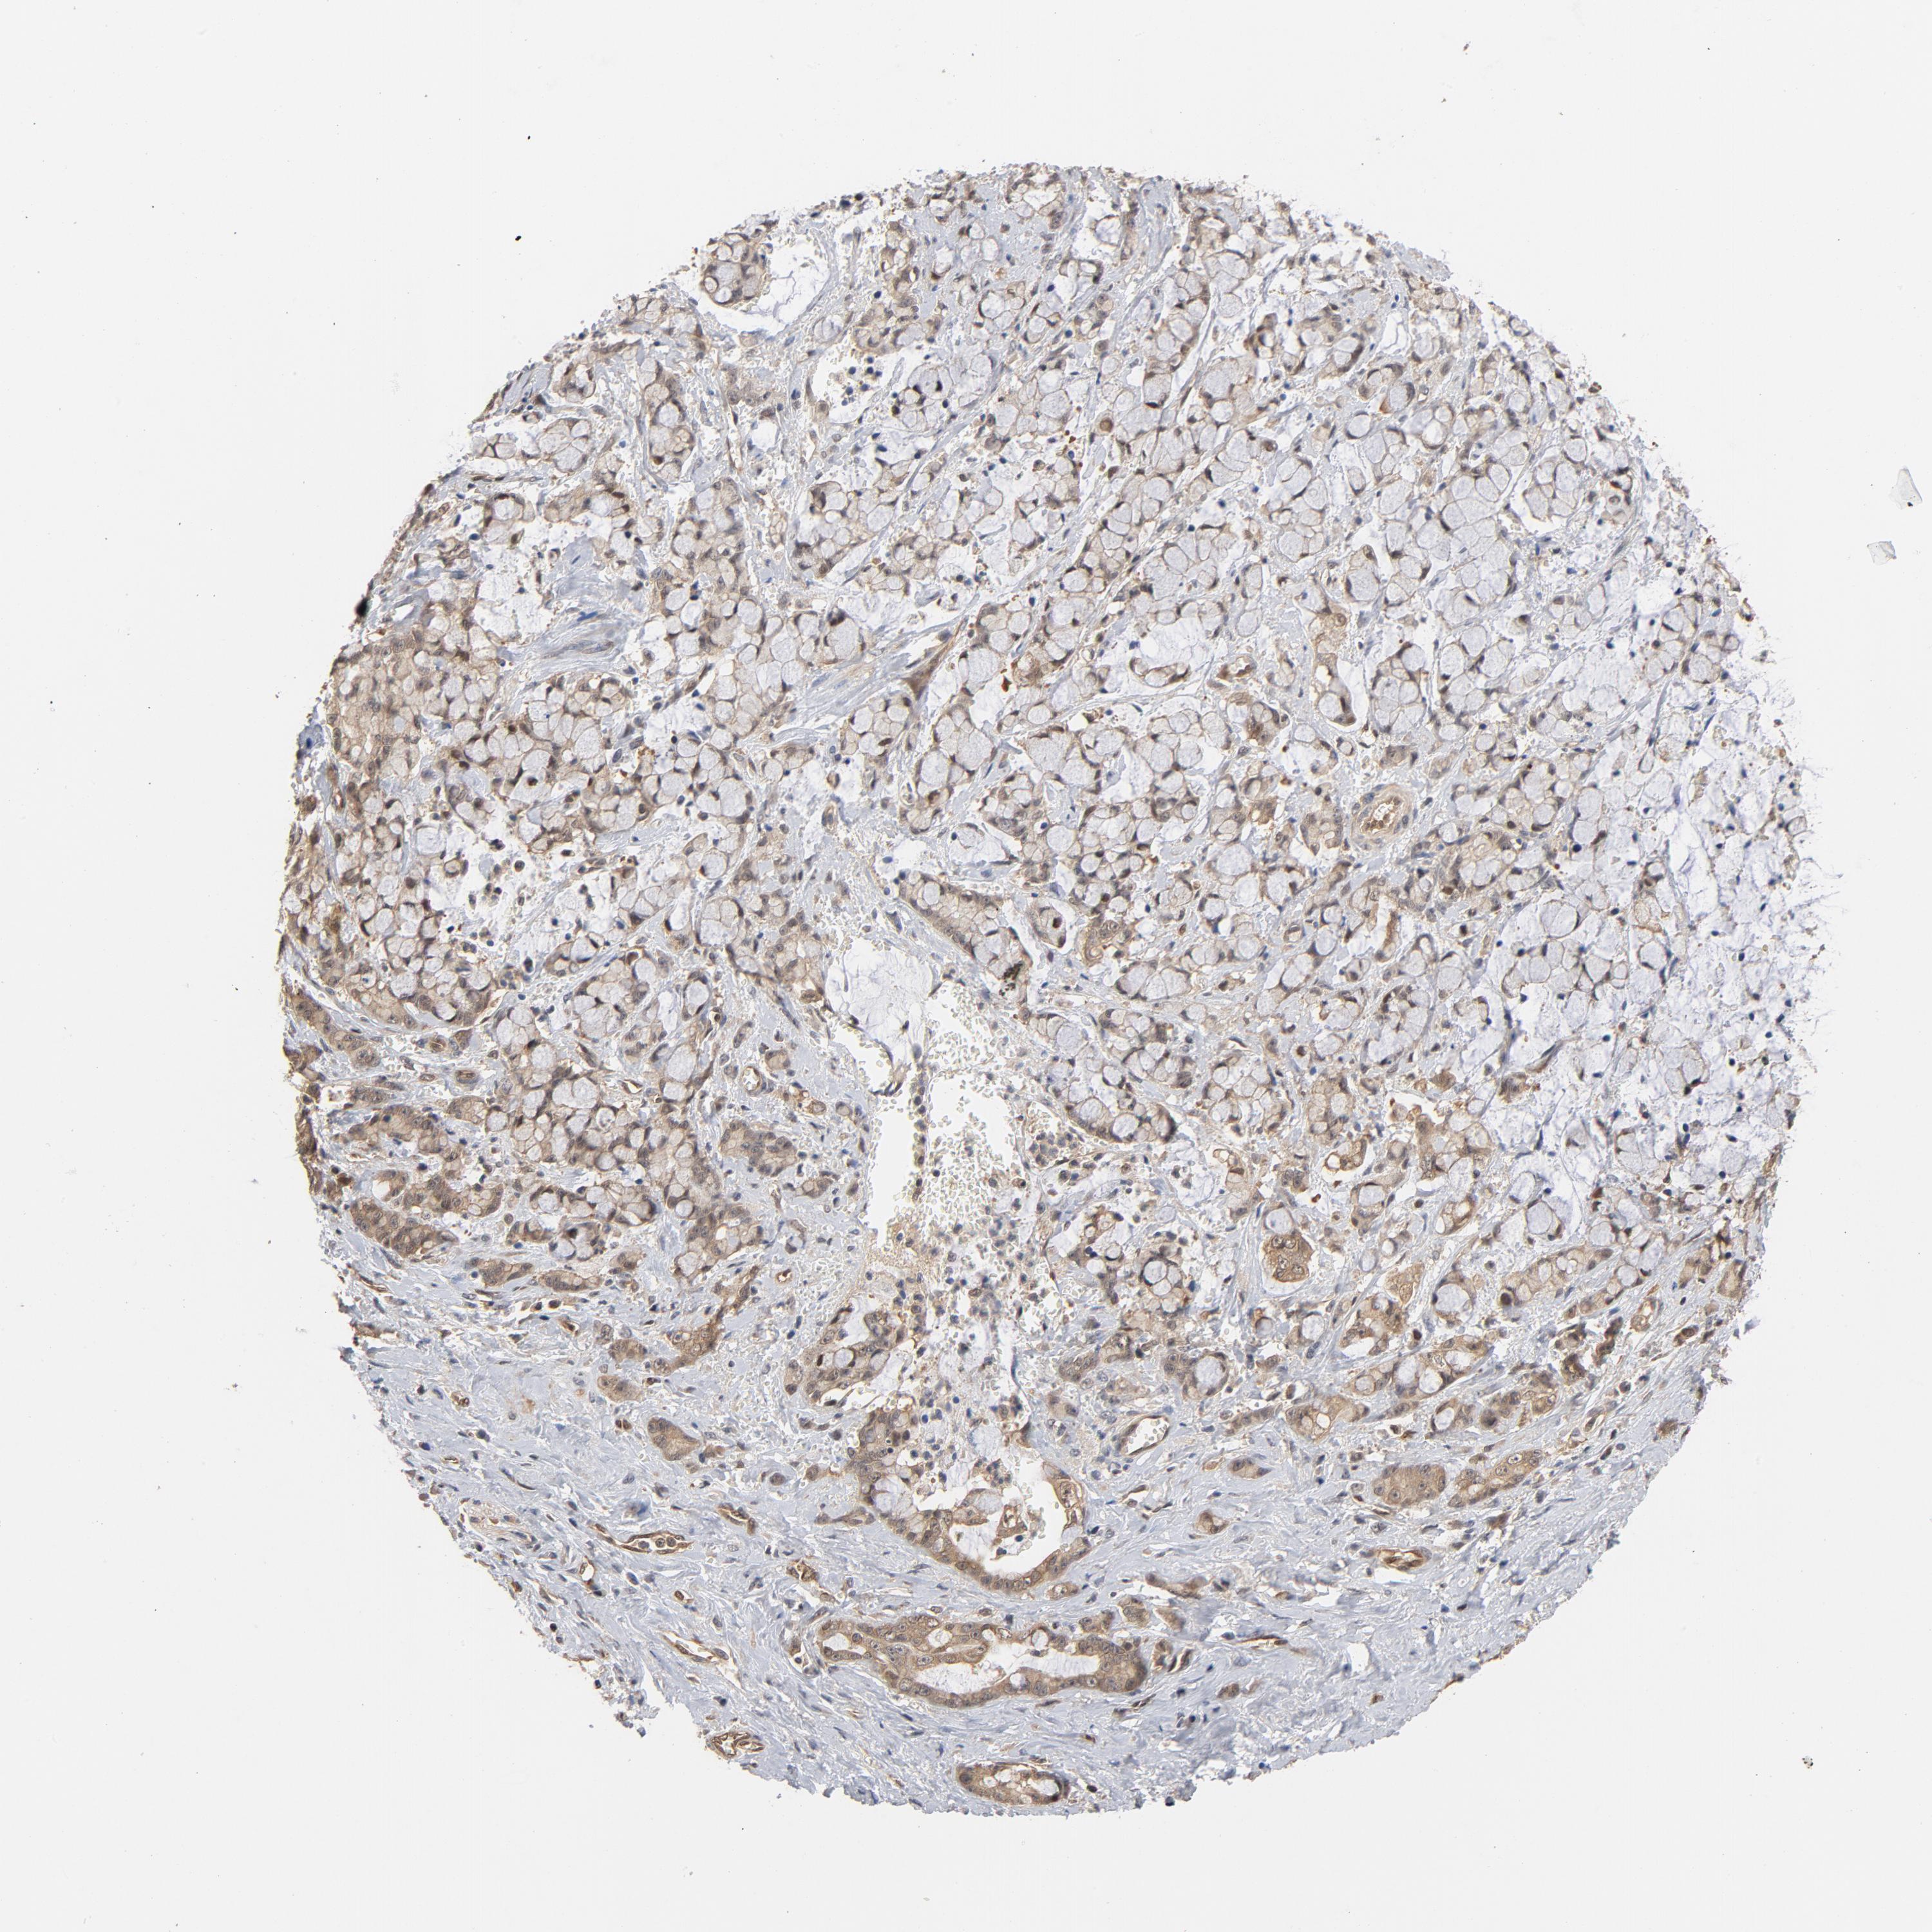

PANCREATIC CANCER - Protein expressioni

A mouse-over function shows sample information and annotation data. Click on an image to view it in a full screen mode. Samples can be filtered based on level of antibody staining by selecting one or several of the following categories: high, medium, low and not detected. The assay and annotation is described here.

Note that samples used for immunohistochemistry by the Human Protein Atlas do not correspond to samples in the TCGA dataset.

Antibody stainingi

Antibody staining in the annotated cell types in the current human tissue is reported as not detected, low, medium, or high, based on conventional immunohistochemistry profiling in selected tissues. This score is based on the combination of the staining intensity and fraction of stained cells.

Each image is clickable and will lead to virtual microscopy that enables deeper exploration of all samples and also displays staining intensity scores, fraction scores and subcellular localization as well as patient and tissue information for each sample.

Antibody HPA003928

Antibody CAB004214

Staining

High

Medium

Low

Not detected

Intensity

Strong

Moderate

Weak

Negative

Quantity

>75%

75%-25%

<25%

None

Location

Nuclear

Cytoplasmic/membranous

Cytoplasmic/membranous,nuclear

Adenocarcinoma, NOS

Adenocarcinoma, metastatic, NOS